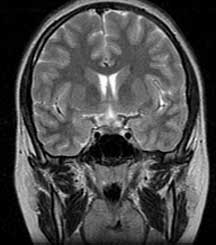

T2 coronals

Subtle thickening of the pituitary infundibulum (arrow).